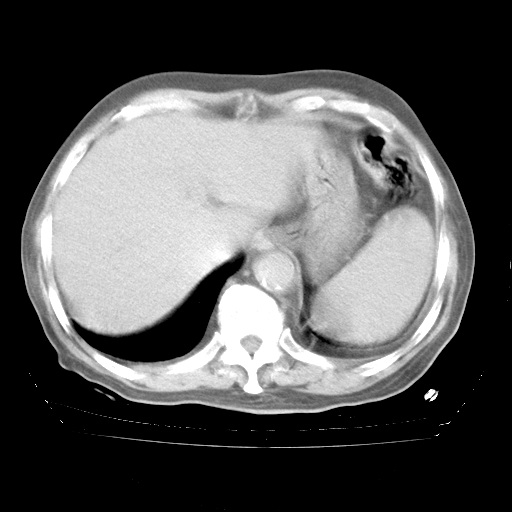

4月28日肺部CT

个人阅读4.14日肺部CT平扫:纵隔窗无异常,但肺窗示:双下肺内、后基底段有片絮状侵润影,部位以后基底段为著,以间质改变为主,呈急性肺泡炎征像,和首次住院影像学有相似之处。仅是个人读片,明日请相关专家再读片哈。其它建议同上。

1、108#的是4月14日的胸部CT(发此贴时还没看着28日的CT)。14日的胸部CT其实已经出现改变(如108#所述),个人认为28日的胸部CT除纵膈窗疑似有双侧胸膜增厚或少量胸积液(可行胸部B超明确)外,与4月14日对照病变有所加重;2、已经给予“异烟肼、利福平、乙胺丁醇”抗痨治疗?如果是,甲强龙80mg可缓慢减量;如果环磷酰胺已停用,暂不使用;3、中性粒细胞92%,明显升高,目前体温情况?注意合并细菌感染可能,使用左氧氟沙星情况下,是否联用B-内酰胺类抗菌药物?另外是查免疫全套非风湿全套。

今请临免主任会诊后认为:4月14日胸部CT已有双下肺间质性改变。患者病情复发多系激素减量过快不正规所致。目前甲强龙80mg/日,一周后酌情开始减量,不易过快。环磷酰胺若已停用,暂不使用。他同意目前抗菌药物使用,但应考虑是否加用B-内酰胺类抗菌药物(中性细胞明显增高);2、结核复发目前依据不足;3、若免疫全套各项指标正常,考虑多系特发性肺间质炎可能大。4、加强支持,并注意保护胃黏膜。

今上午去请教了临免、呼吸主任:1、介绍病史和阅读系列胸部CT一致认为:患者肺结核不考虑,仍为肺间质纤维化,目前处于急性肺泡炎阶段。2、若仍发热,可将甲强龙增至:80mg Bid静滴,同时鉴于中性增高,合并细菌感染可能,继续左氧氟沙星治疗,再联用B-内酰胺抗菌药物,如头孢哌酮--舒巴坦;3、停用抗痨药;4、目前甲强龙每日剂量160mg ,体温正常后再酌情减量;目前暂不用免疫抑制剂;4、不建议使用免疫增强剂等;5、加强支持治疗,鼓励患者进食;5、注意随访肝、肾功及血常规情况;6、因患者目前激素用量较大,加用胃黏膜保护剂,防止消化道出血可能。